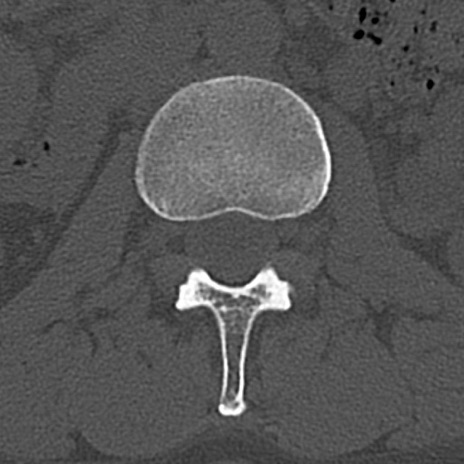

腰椎CT

横断像と矢状断像